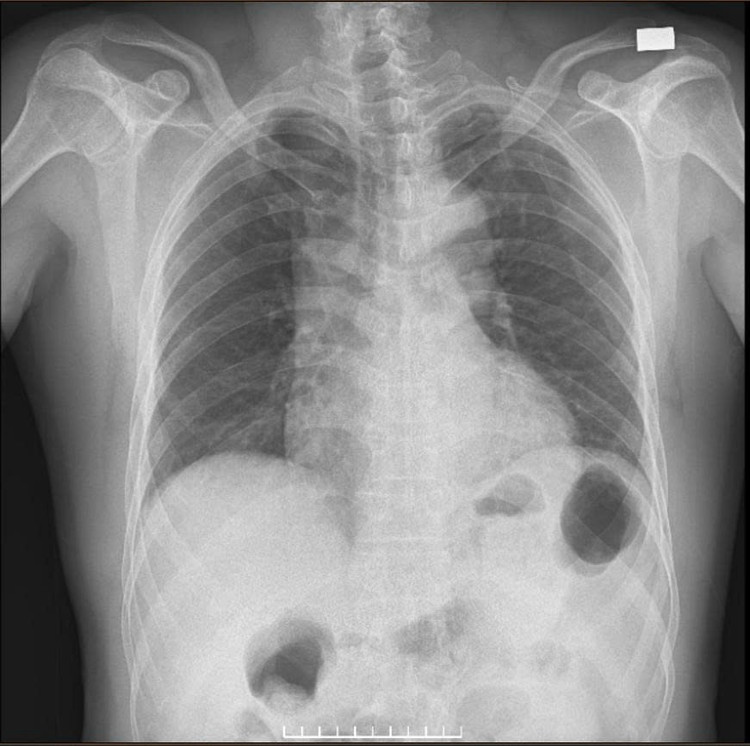

Kết quả cận lâm sàng: Troponin I tăng cao - dấu hiệu gợi ý tổn thương cơ tim; Bạch cầu tăng, creatinin tăng nhẹ. X-quang ngực: Hình ảnh trung thất giãn rộng, bóng động mạch chủ bất thường. Điện tâm đồ không điển hình của nhồi máu cơ tim cấp.

X-quang ngực: Hình ảnh trung thất giãn rộng, bóng động mạch chủ bất thường - Ảnh BVCC